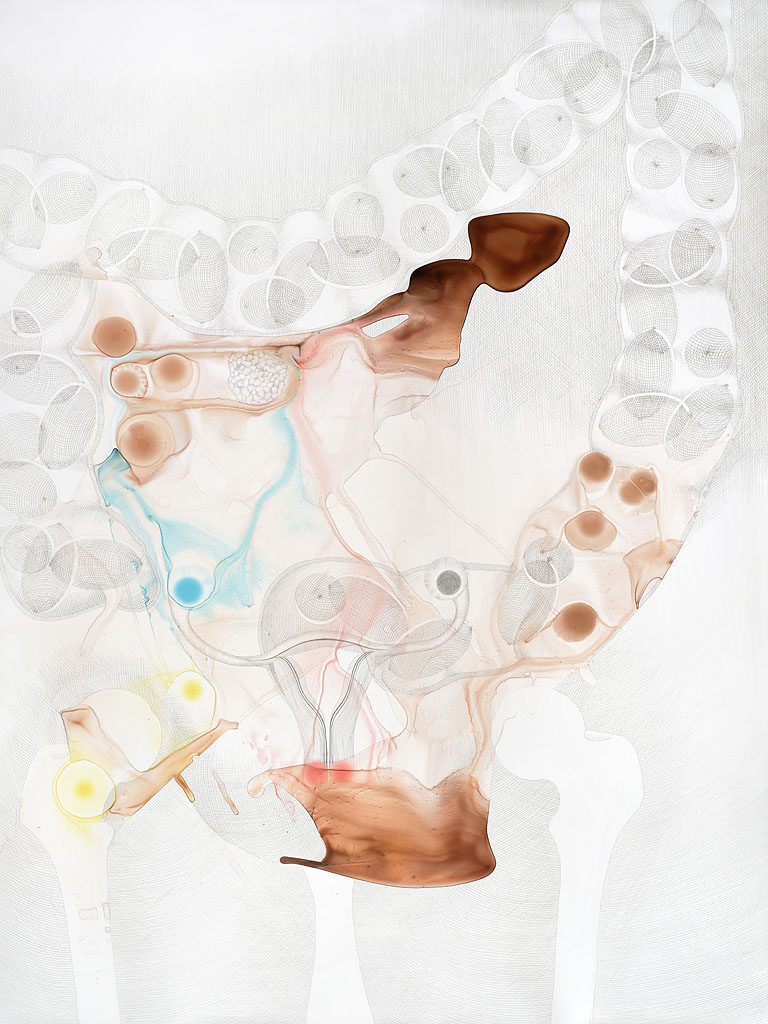

While working on several projects and experimenting with various media, somewhere along the way I developed an interest in medical illustration as a visual representation of the human body. I began reading philosophy texts on the human body and how we define it. I am very much interested in the fact that a medical illustration can never be an objective representation of the body. We all have subjective visceral experiences that differ from person to person, and these cannot be visually represented without something being lost in translation.

Ever since I became interested in this topic, I’ve been creating drawings and paintings that mix technical scientific images with things that are generally not meant to be there: abstract inkblots, random humorous intrusions and additions, sudden changes in rendering… The work tries to hint at things that medical illustration cannot represent—things that are very much embodied. Human experiences of pain, love, confusion, fear, happiness—all of these kinds of things reside in the body.

Photos of my work are available on my website but seeing those is not the same as seeing the work itself. Some of my drawings and paintings are several feet tall with unusual surfaces and textures that require movement while viewing. Regarding supporting my work, all of my paintings are for sale. If you are in the Chicago area and might be interested in purchasing a piece, you are welcome to come for a studio visit.